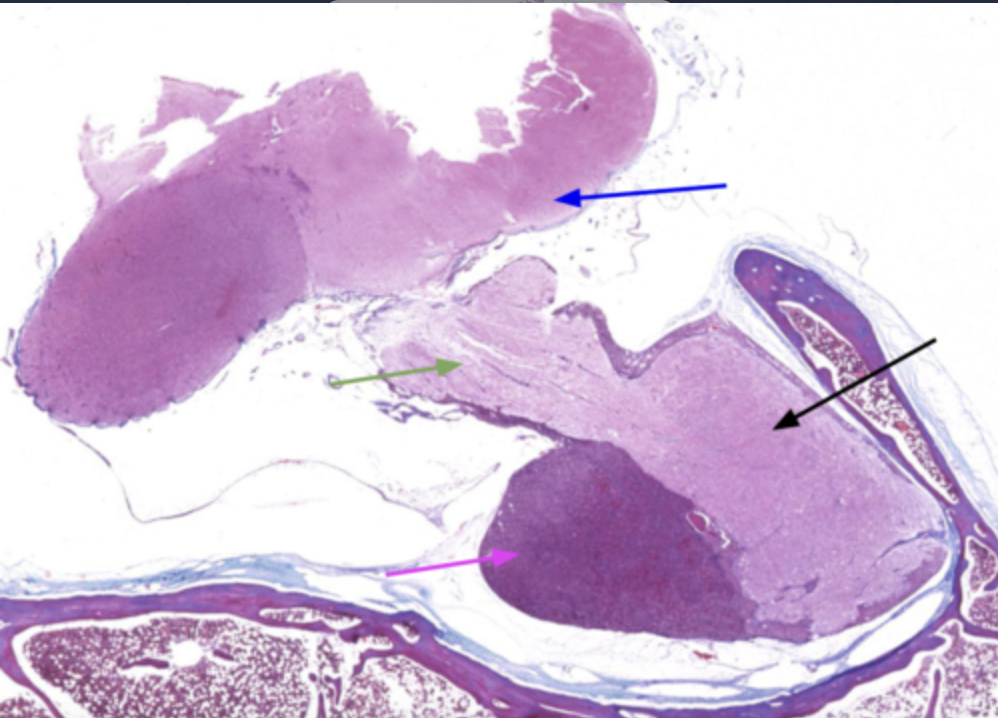

What is the magenta arrow pointing to?

adenohypophysis

What is the black arrow pointing to?

Neurohypophysis

The adenohypophysis is what in color when compared to the neurohypophysis

Darker in color

What is the green arrow?

Infundibulum

What is the blue arrow?

Hypothalamus

Why is the adenohypophysis darker than the neurohypophysis?

Because it has a variety of cell classes responsible for producing many hormones. It also contains a lot more blood vessels than the neurohypophysis

Why is the neurohypophysis lighter?

Because it’s primarliy made up of unmyelinated axons from different neuron bodies

The black arrow points to what?

What does the red line indicate?

What structure is indicative of the blue line?

Adenohypophysis (anterior pituitary)

The green arrow is pointing to?

Neurohypophysis (posterior pituitary)